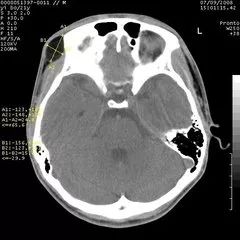

CT与普通体层摄影的区别在哪

CT头颅扫描图像